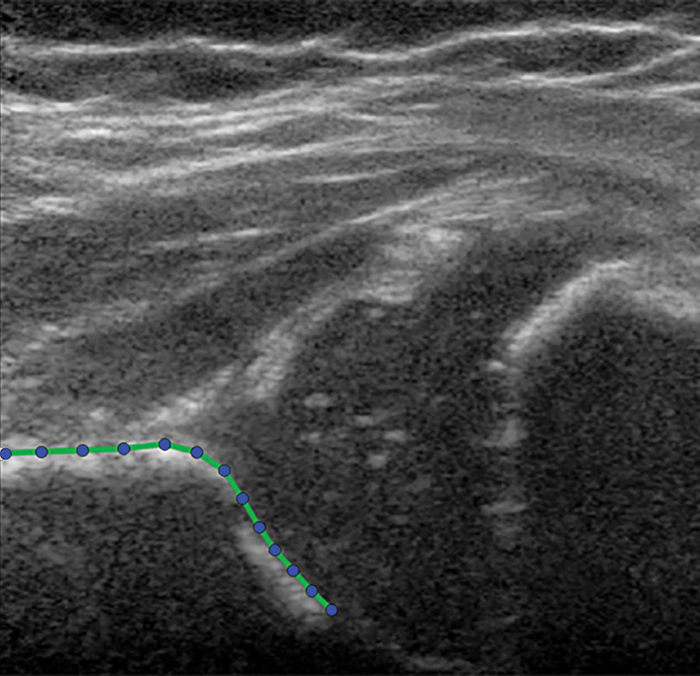

图像:3个月大女婴的髋关节图像。未使用造影剂。所述髋关节是用髋臼形状模型勾勒出来的,包括13个点。

用超声进行统计形状建模是一种替代方法,它通过多个参考点来量化髋关节图像的形状,每个参考点在二维超声图像中有一个X坐标和一个Y坐标。与现有的预测模型相比,它具有潜在的优势。